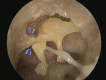

An overview of endoscopic ear surgery in 2018

Objective: To provide an overview of Endoscopic Ear Surgery, its development, principles, and penetration in otology practice in 2018.

Results: The number of publications on use of endoscope has increased from 6 in 1990 to an accumulated total of 451 in 2018. There has been a clear shift in the area of interest away from diagnostic endoscopy, to endoscope-assisted surgery, and lately, to transcanal endoscopic ear surgery (TEES). Survey results further documented the increased awareness of the value of the endoscope and its increased use in clinical practice.

Conclusion: TEES has gained traction as a subject of research interest and in clinical practice and has lately dominated the discussion on the use of endoscope in otology.